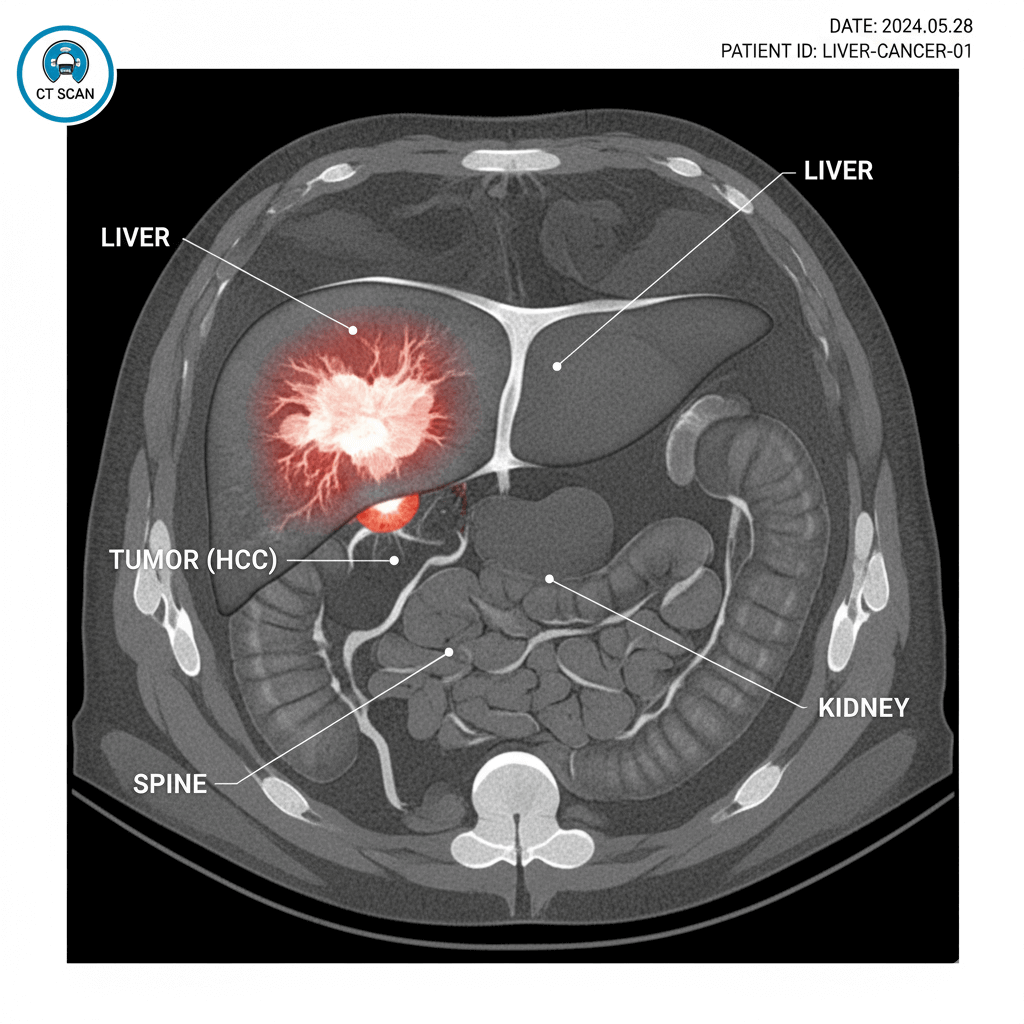

곧바로 간 CT 검사를 진행하였는데, 암이 의심된다는 소견을 받았습니다.

소견서를 갖고 MRI검사를 추가로 진행하였는데

검사결과 1.3cm가량의 혹이 간 우측에서 발견되었습니다.

정확한 검사를 위해 대학병원으로 진료를 예약하여 CT와 MRI를 순차적으로 진행한 결과

간암 확진을 받았습니다.